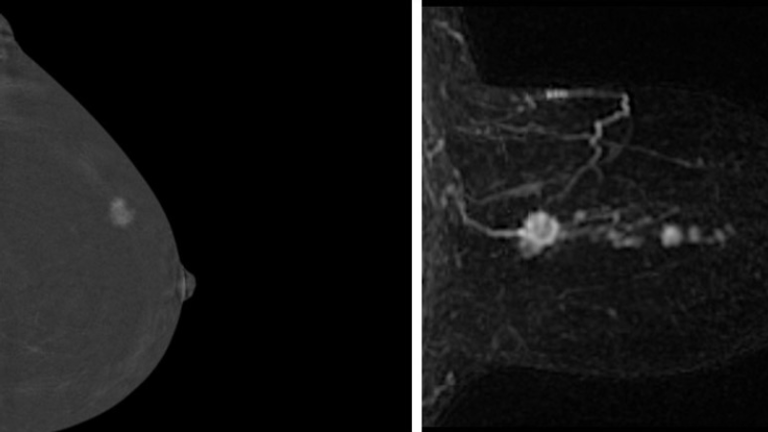

As part of the trial, Ms Duffield had an AB-MRI scan, a faster type of MRI, which identified a small lump deep inside one of her breasts.

The two methods examined in the trial were contrast-enhanced mammography (CEM), where dye is used to make blood vessels more visible, and AB-MRIs.